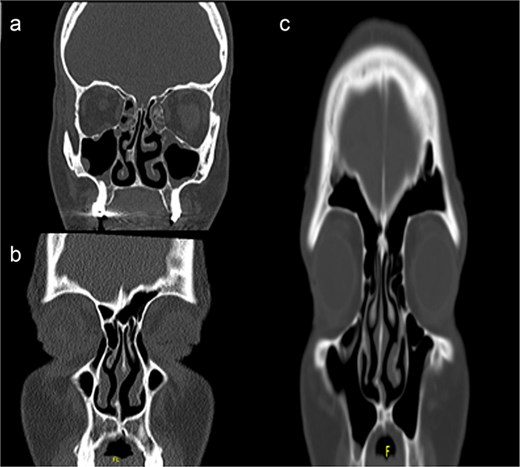

Surgical technique: The intra nasal endoscopic septoplasty

Our INES technique is specifically indicated for selected unilateral septum deviation. The procedure is particularly suitable for unilateral deviations with associated septal spurs, corresponding to Mladina type 5 and 6 deviations that affect the nasal patency (Fig. 1).

Computed tomography scans showing unilateral nasal obstruction caused by septal spurs, corresponding to Mladina type 5 (lateral nasal wall contact) and type 6 (bilateral spurs) nasal septum deviations.

We classified septal deviations using Mladina’s classification system, which divides DNS into seven different categories [8]. When the deviation impacts the inferior turbinate region, specifically type 5 deviations (unilateral deformity of the basal septal crest) and type 6 deviations (prominent unilateral basal septal crest with contralateral septal deformity) are the target of our approach.